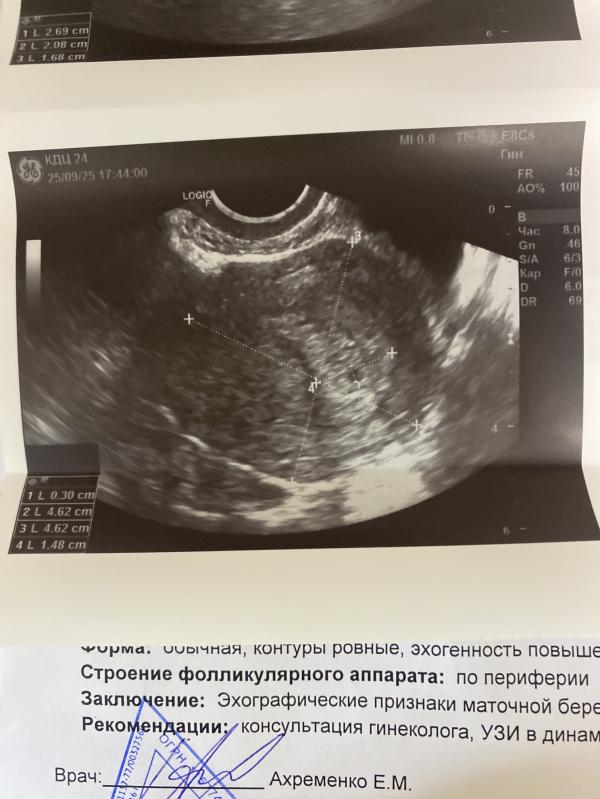

Сходила я на узи пя нашли , но нет желточного мешочка и меня смутил размер желтого тела . В женской когда я обращалась с выделениями мне делали узи и там намерили желтое тело 18 мм